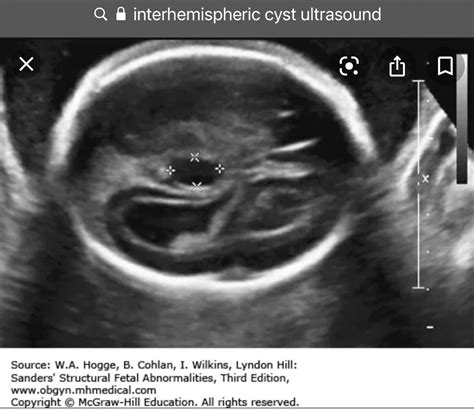

• Obstetrics and Gynecology: Monitoring fetal development and assessing the health of reproductive organs.